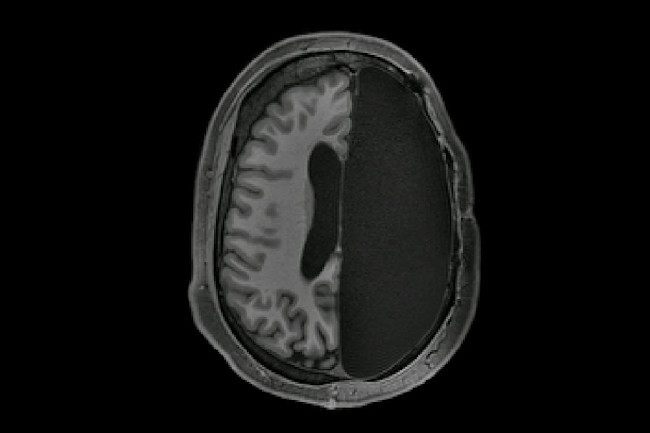

Deep brain stimulation (DBS) is a growing field in neurosurgery that has given hope to people with debilitating conditions. They excel at everything they do with a positive vibe and some rocking compassion. The pillows NOOK IN THE BRAIN TOUR @ 鹿児島 SR HALL 終了しました。どうもありがとうございました!!今後のツアーも楽しく高齢者の方とふれあっていきたいと思います!写真はMCで言っていた公園で食べたサンドイッチ!.